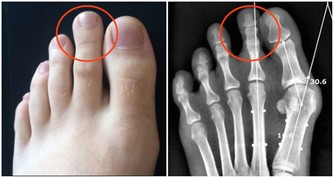

除了體溫升高,發燒還往往伴隨感覺冷、皮膚發紅發燙、頭痛、身體痛、疲勞虛弱、食慾不振、心率加快、脫水等症狀。